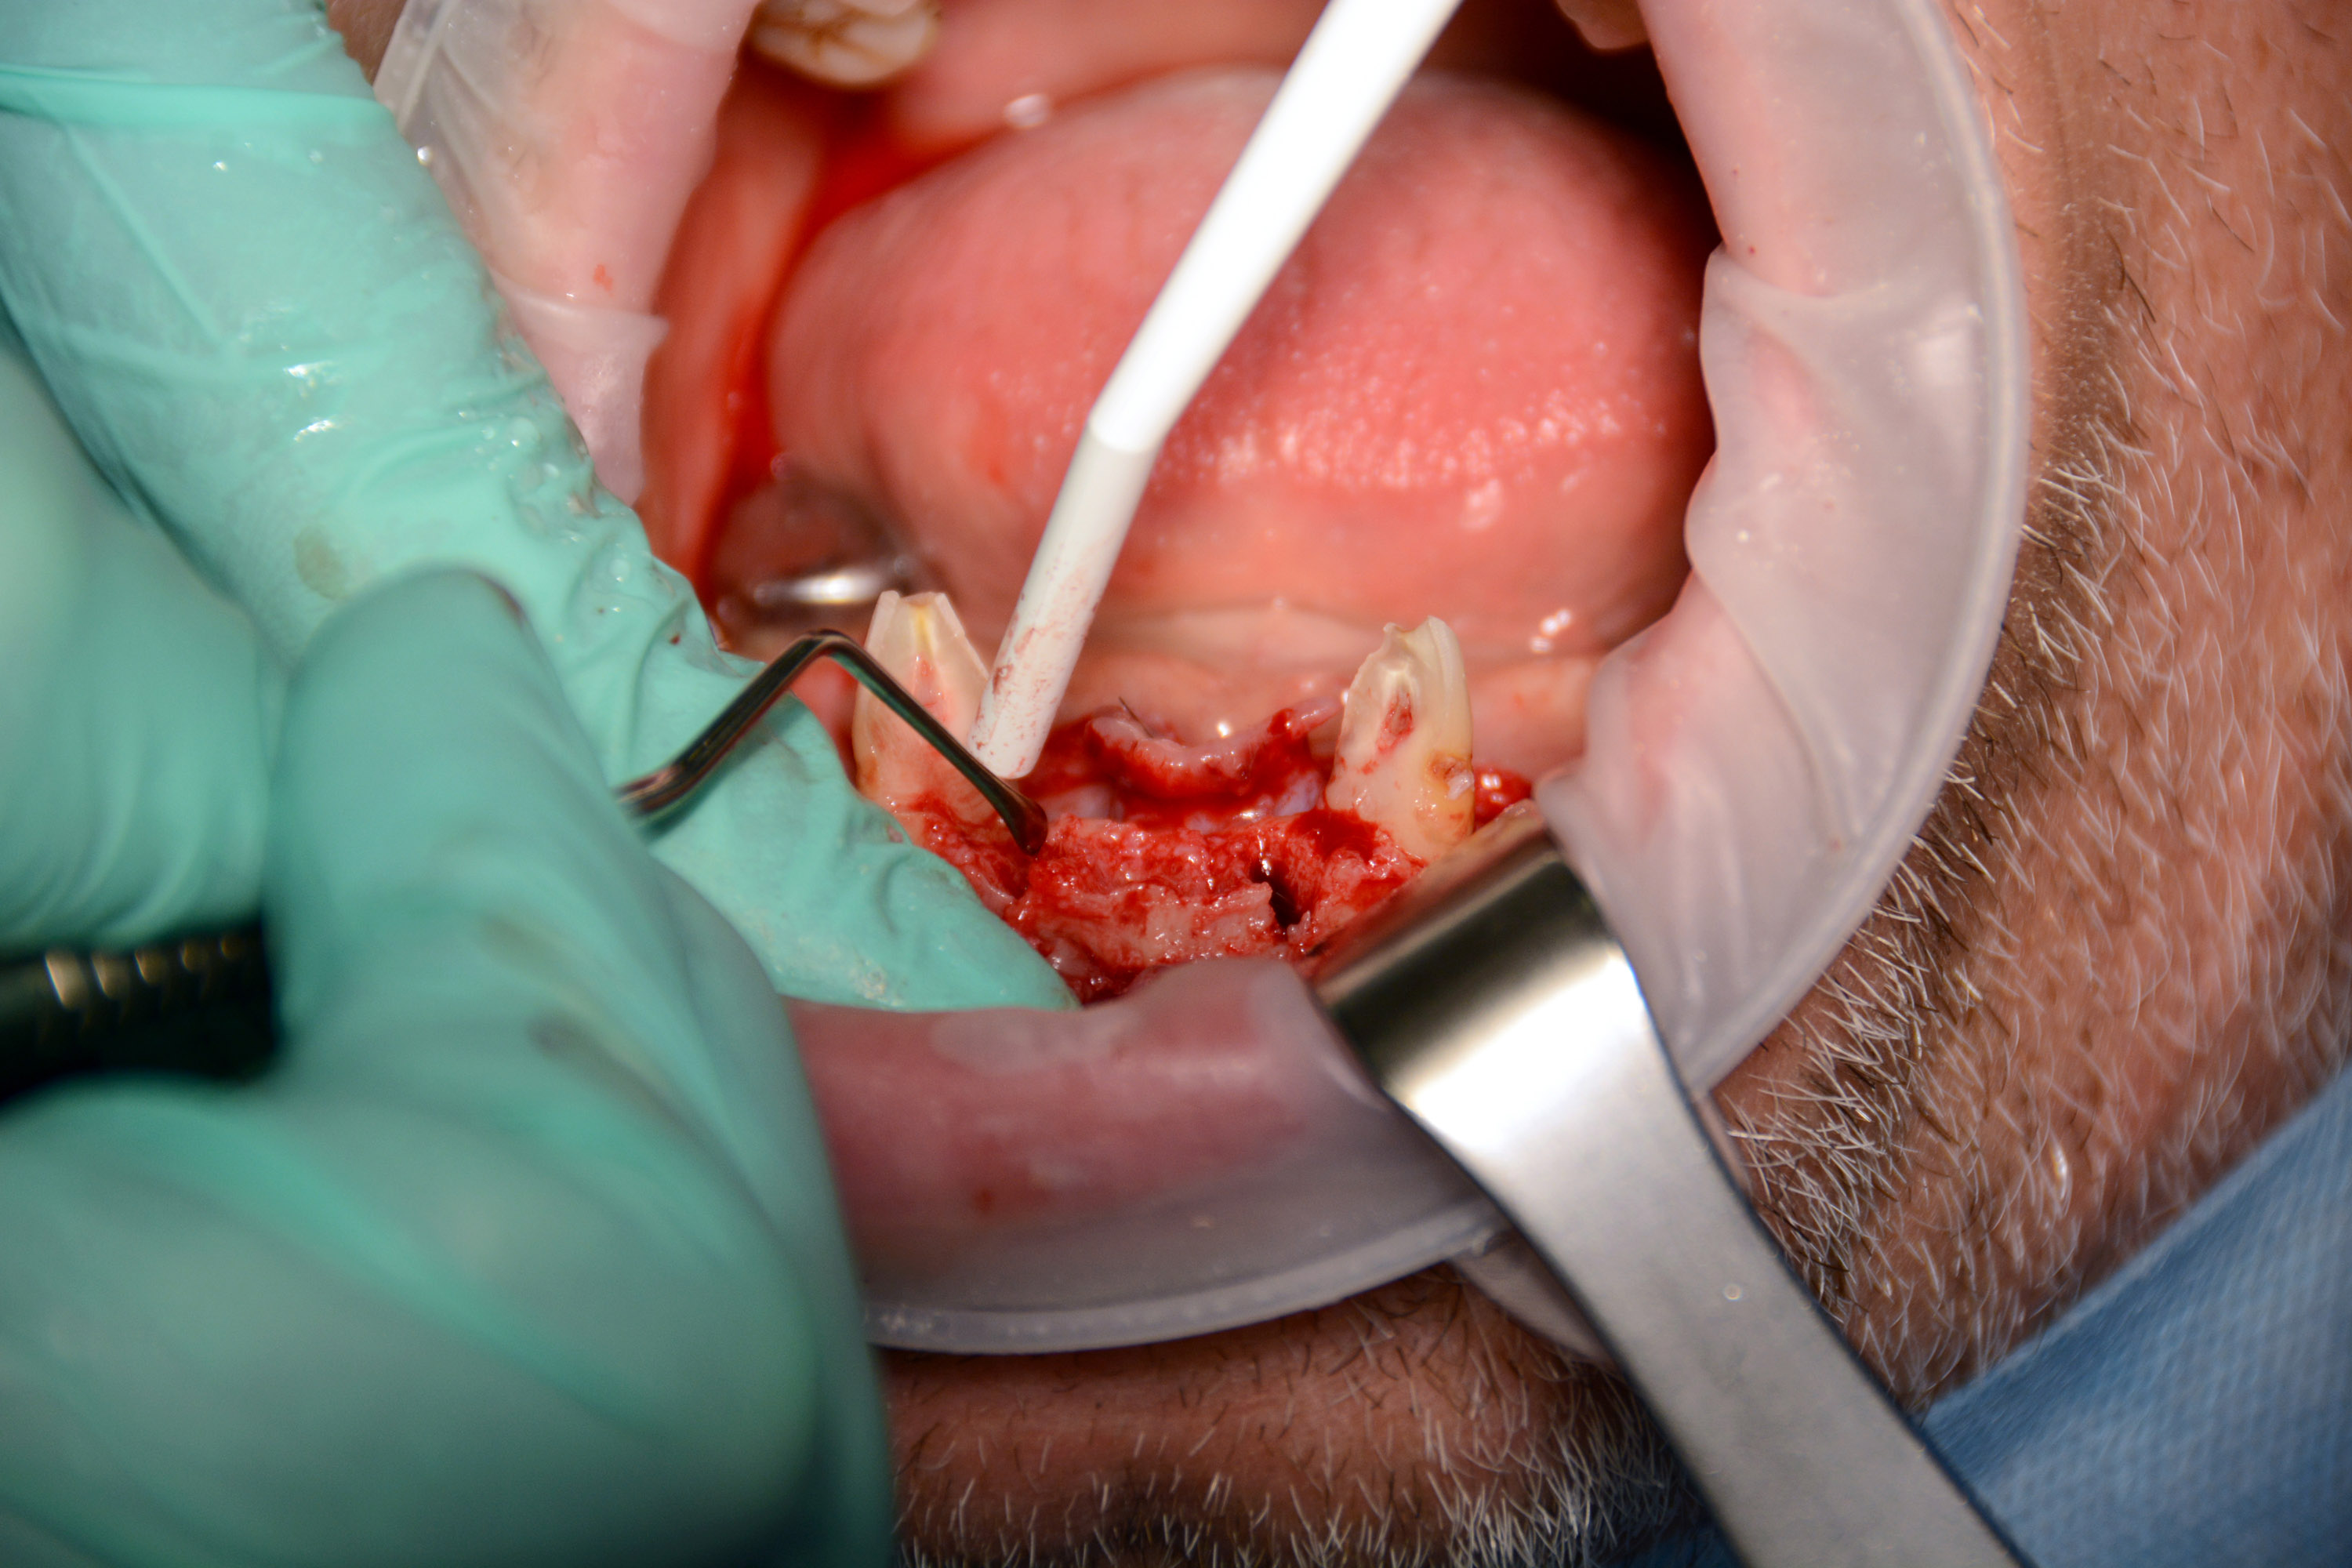

Pierwszy zabieg polegał na usunięciu 6 zębów w żuchwie i wprowadzeniu 4 implantów z wykorzystaniem szablonu chirurgicznego do pełnej nawigacji. Bezpośrednio po zabiegu zostały przykręcone multiunity do implantów i osadzony tymczasowy most.